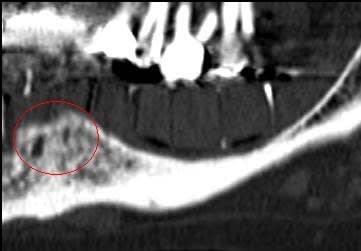

bon ça c'est fait!

dans le cas présenté, j'ai d'abord mis du perioglass (billes) que j'ai compacté "légèrement" à la compresse+Ostéotome pour "bloquer" la partie osseuse surélevée, puis j'ai mis le VitalOs que j'ai lui aussi "aplani" à la compresse + Ostéotome.

Il maintient les billes, et les deux corticales et sert de membrane